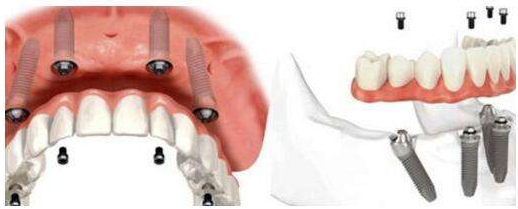

All-on-N用四个种植体即可支撑半口牙桥,种牙当天安装固定牙桥。如图示,植入4颗人工牙根固定半口牙桥,一次完成。其中,后牙2颗人工牙根为斜拉式设计,可避免上颌窦及下颌神经等危险区。即使在骨量最小的情况下也可实现稳定性。》》》推荐阅读:种植牙是不是越贵越好?